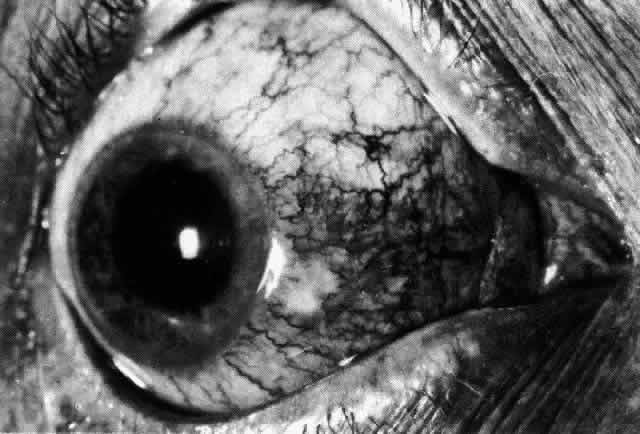

The object of slit lamp examination is to determine the depth and nature of scleral and episcleral conditions and the presence of corneal changes. The changes seen are drawn in the records. With the use of diffuse light with a neutral density filter, the vascular networks of both eyes are examined in detail to determine the layer in which the vessels show maximum congestion, the infiltration of episcleral tissues, and the edema of sclera, episclera, or subconjunctival space. Slit lamp examination is also used to ascertain the nature and depth of any corneal changes; the presence of scleral edema (for which it may be necessary to blanch the superficial tissues with epinephrine 1:1000 or phenylephrine 10%); the nature of any episcleral infiltration or mass; and the presence of cells in the anterior chamber or vitreous and posterior synechiae. The red-free (green) filter is extremely valuable in confirming the areas of maximum congestion and whether any areas are totally avascular. Because this is an important physical sign and is easily missed, examination in red-free light should be routinely performed. The green light brings the vessels into very sharp contrast with the background and enables the position of maximum inflammation to be determined with certainty. It also enables the paths and configurations of the vessels to be followed and will show lymphocytic infiltration of the episcleral tissue as yellow spots; this often indicates that the condition is more extensive than previously supposed (Fig. 8).

Fig. 8. Examination in red-free light. Blood vessels brought into sharp contrast reveal areas of lymphocytic infiltration in episcleral tissues, in this case due to herpes simplex virus.